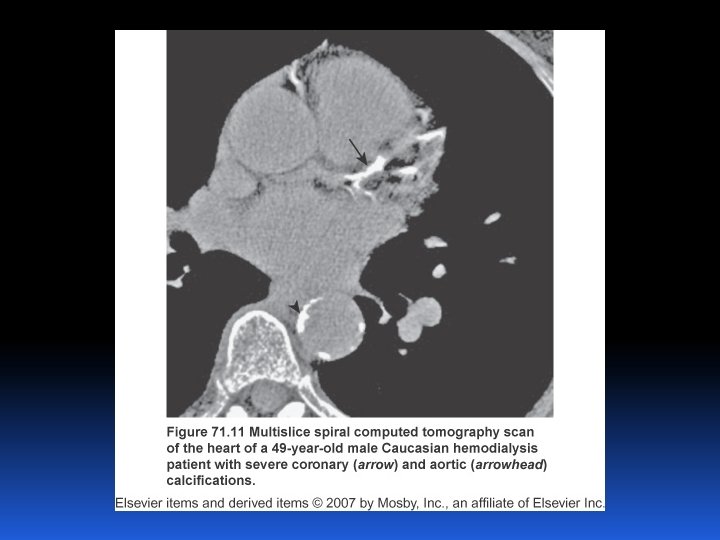

STADI MALATTIA RENALE e CARDIOVASCOLARE Insuff. Renale cronica terminale Insuff. Renale Cronica ( FG) Albuminuria Proteinuria Anziano, obesità Diabete Mellito, Press. Arter. Malattia Renale Cronica Stadio Scompenso cardiaco finale Progressione Eventi malattia cardiovascolare (MCV) MC Insuff. Ventricolare sx Inizio “A rischio” Anziano, obesità Diabete Mellito, Press. Arter. Malattia Cardiovascolare Sarnak MJ & Levey AS, Am J Kidney Dis, 2000

Il rischio della malattia renale cronica va ben al di là del rene Rischio Relativo 3. 4 4 2. 8 3 2 2 1. 4 1 0 No lieve/moderata/severa insufficienza renale avanzata